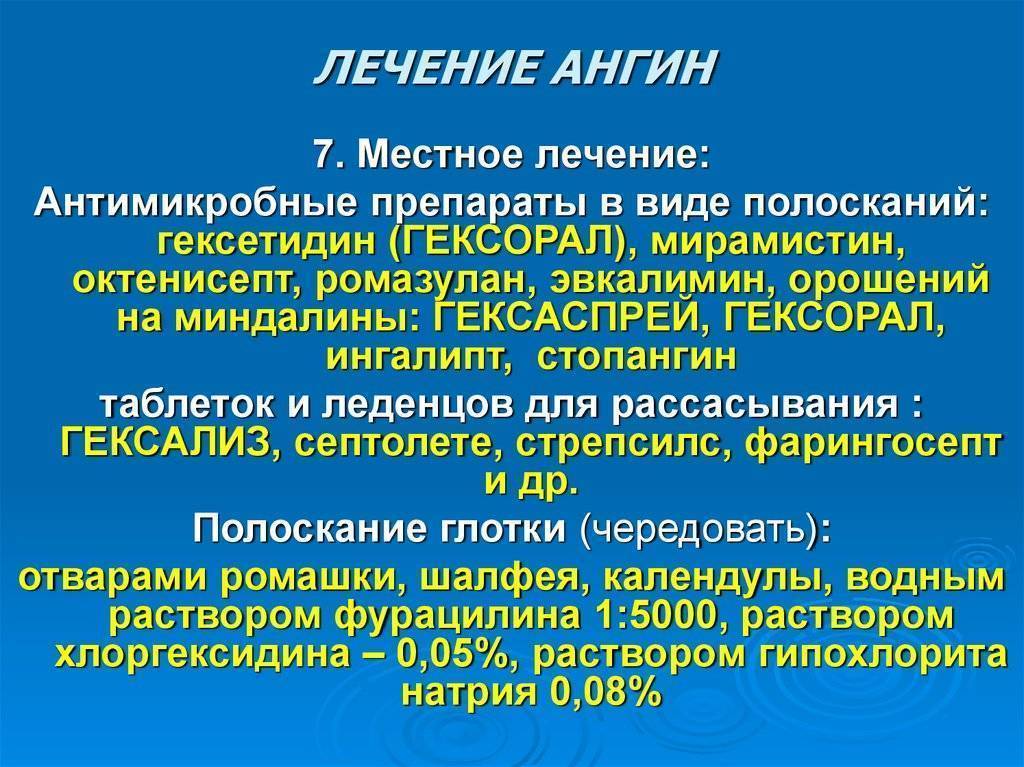

- Местное лечение болезни. Данный метод является обязательным условием терапии. Полоскания и орошения горла направлены на дезинфекцию полости и уменьшению симптоматики. К самым эффективным местным средствам относят: полоскания горла раствором Фурацилина, содовым и солевым раствором с йодом.; полоскания настоями лекарственных трав в виде ромашки, календулы, шалфея; орошение горла раствором морской соли; орошение горла лекарственными средствами в виде Мирамистина, Гексорала, Каметона; рассасывание противовоспалительных и антибактериальных таблеток в виде Граммидина, Стрепсилса, Лизобакта, Фарингосепта.

Нужно чётко следовать всем рекомендация лечащего педиатра для скорейшего выздоровления малыша. Эффективное лечение ангины подразумевает обильный приём жидкости, жаропонижающих, антибиотиков, эубиотиков, антигистаминных средств, полоскания горла и витаминотерапии.

Но полоскание горла это только 1 из вспомогательных способов, т. к. основное лечение заключается в приёме антибактериальных средств

Один из способов лечения ангины — это полоскание горла для детей старшего возраста и обработка аэрозолями и спреями маленьких детей. Но полоскание горла это только 1 из вспомогательных способов, т. к. основное лечение заключается в приёме антибактериальных средств.

- Для полоскания горла у детей старше трёх лет можно использовать спреи Гексорал, Люголь и Тантум Верде, а после шести лет — Ингалипт и Гексаспрей.

- 0,01% раствором Мирамистина, слабым марганцовым раствором, перекисью водорода — 2 столовые ложки на стакан воды, раствором Йодинола — одна столовая ложка на 1 стакан тёплой воды и растворив в стакане воды 2 таблетки фурацилина.

- Хорошим обеззараживающим свойством обладают отвары растительных трав — ромашки, шалфея, календулы и в виде готовых аптечных сборов этих трав (Ротокан, Эвкар и Ингафитол). Простой раствор соды и соли — по пол чайной ложки и нескольких капель также неплохо обеззараживает.

- Детям постарше при ангине рекомендуют рассасывающие леденцы и таблетки — Стопангин, Гексорал табс, Фарингосепт, Стрепсилс (после пяти лет) и Граммидин.